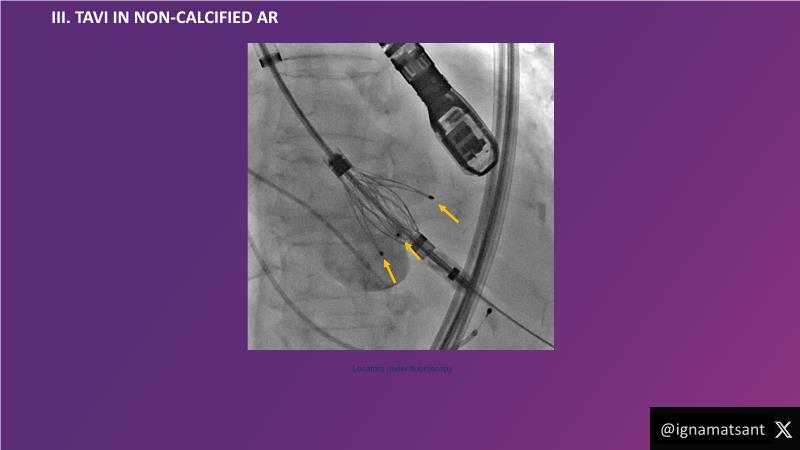

- To learn about the novel Myval next generation THV technology, its key features, procedural and clinical benefits and learn about the clinical data in a vast cohort of patient population

- To understand the CorAlign technique which enables predictable and precise commissural and coronary alignment thus preserving coronary access